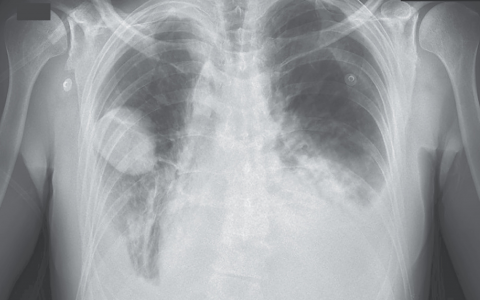

A 58-year-old man who is postoperative day one after a Whipple procedure develops increased shortness of breath. Oxygen saturation is 86% on 2-liter nasal cannula, respiratory rate is 32 breaths/min, and he is using accessory respiratory muscles. He is hemodynamically stable, alert, and oriented.

腹部手术后,该患者存在重新插管的风险。血流动力学稳定,神志清楚。一项多中心前瞻性试验评价了腹部手术后有再插管风险的患者。再插管风险较高的患者被随机分配接受无创通气或辅助供氧。无创通气组需要重新插管的患者明显更少(33%vs. 45%)。在再插管风险较低的患者中,使用高流量鼻插管降低了再插管的风险(4.9%vs. 12.3%)。尚未研究高流量鼻插管与无创通气相比对高危患者的益处。但是,如果无创通气未改善呼吸衰竭或患者出现其他插管指征,如无法控制气道或血流动力学不稳定,则不延迟再插管非常重要。在这些情况下延迟插管会增加死亡率。